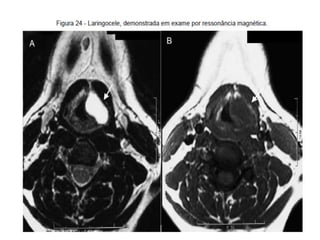

O documento fornece informações sobre como realizar exames de ressonância magnética do pescoço e angiorressonância magnética das carótidas, incluindo parâmetros, programação, anatomia, exames estruturais e funcionais, dicas e protocolos.